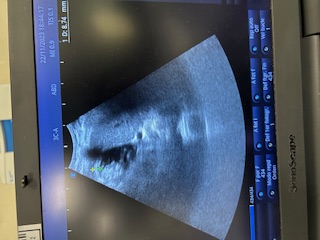

Ecografía: Distensión vesicular con numerosas litiasis intravesicales con pared engrosada de unos 8,74 mm. Ademas, línea hipoecoica en la pared con edema perilesional en área contigua al hígado.